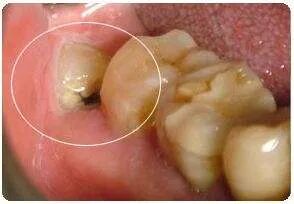

个例牙根弯曲的,在拔除时容易折断,很小块倒没事会被吸收掉,留在里面不用管,如果残留较大就得弄松动去除,不然后期会感染伤口,影响牙槽骨重建。